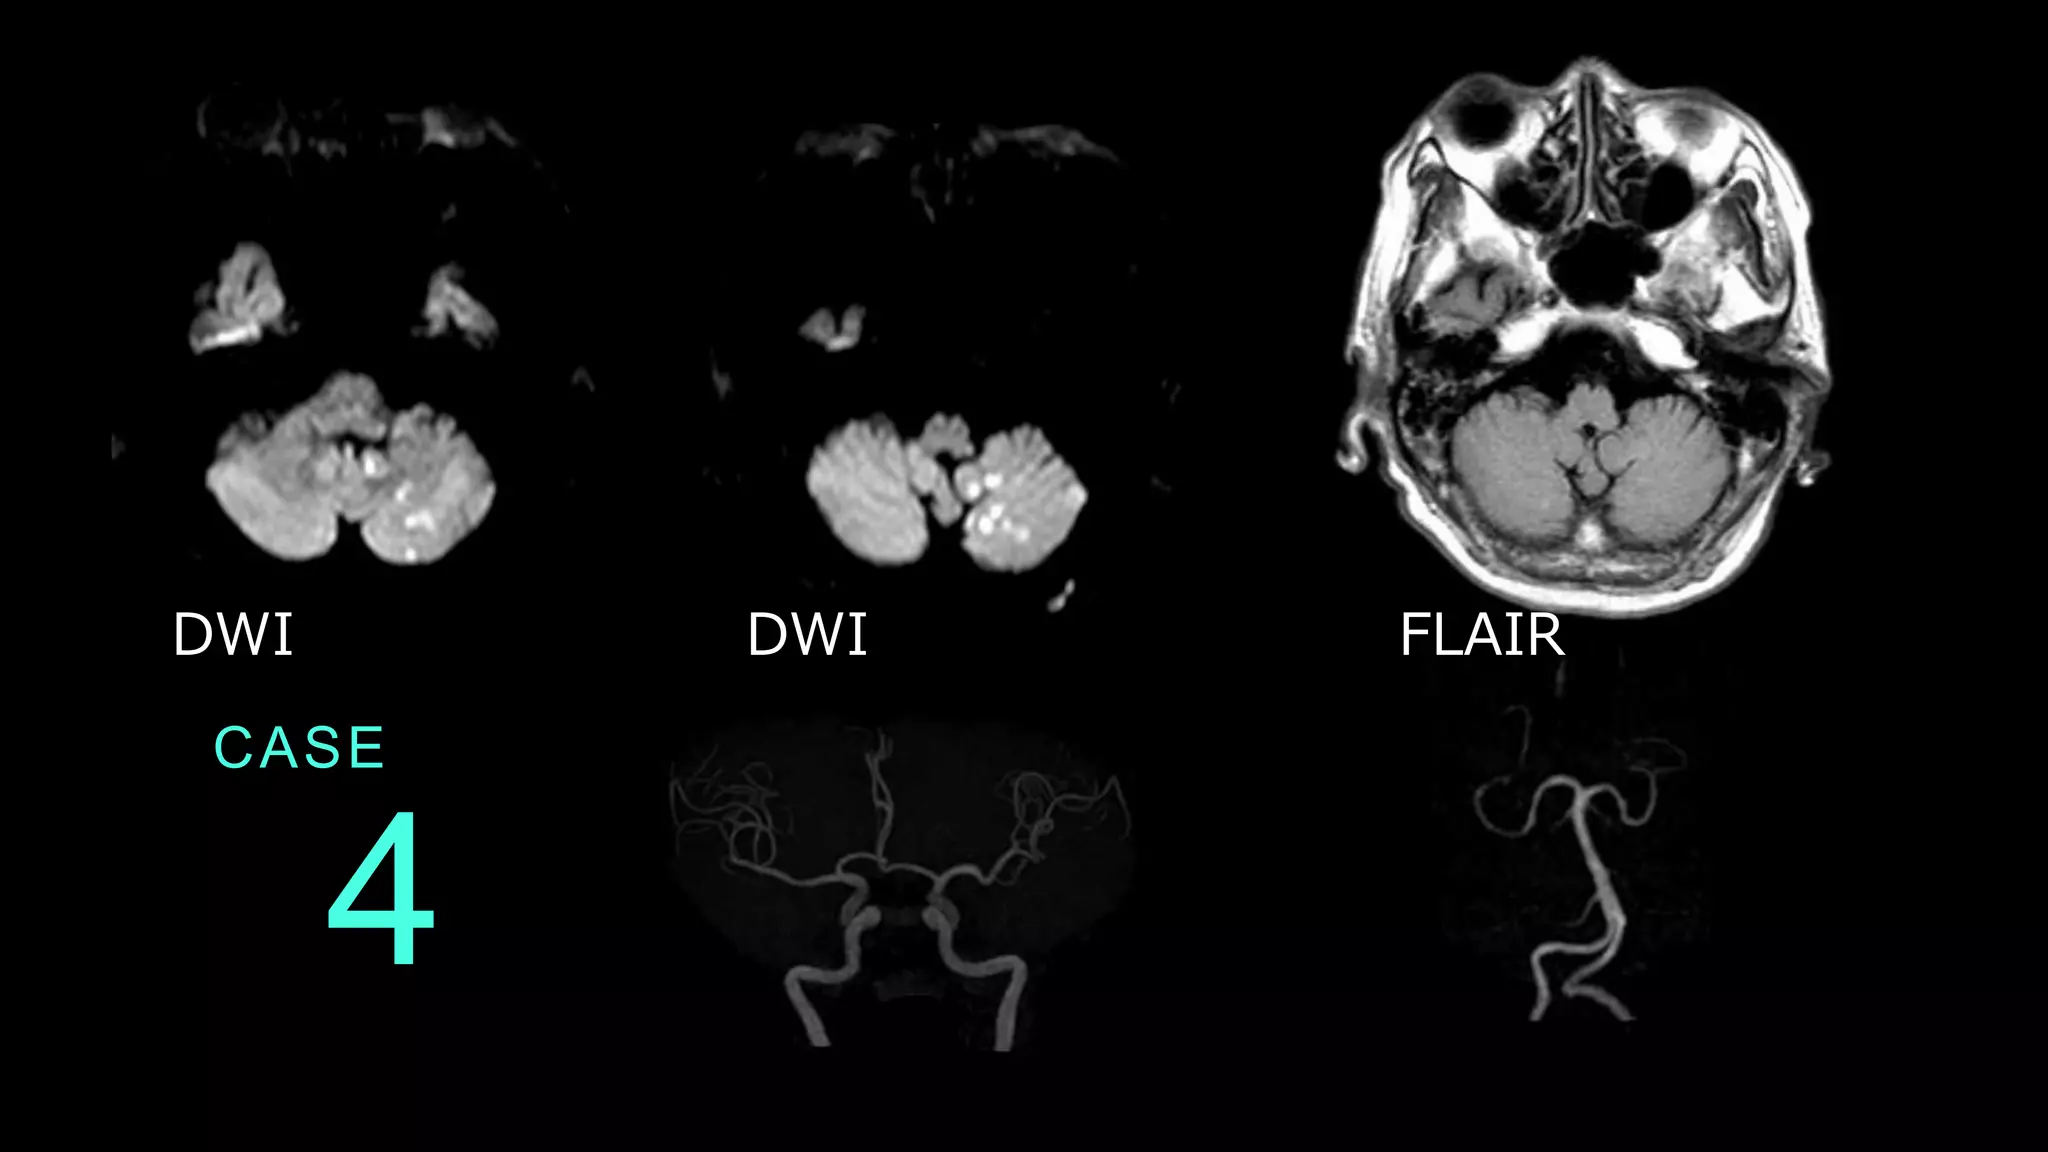

CASE 4 DWI DWI FLAIR

CASE 4 DWIでは、左側小脳に散在性の高信号病変を認める。 同病変はFLAIRでは目立たない。 DWI DWI

FLAIR

CASE 4 MRAでは粗大な血管狭窄病変は、前方循環と後方循環 ともに、目立たない。後方循環系は血管蛇行が認めら れる。

CASE 4 コメント:小脳梗塞症例。小脳への血流は後方循環系 によるので、臨床情報としては、後方循環系の血管狭 窄があるかどうかが知りたい内容になります。